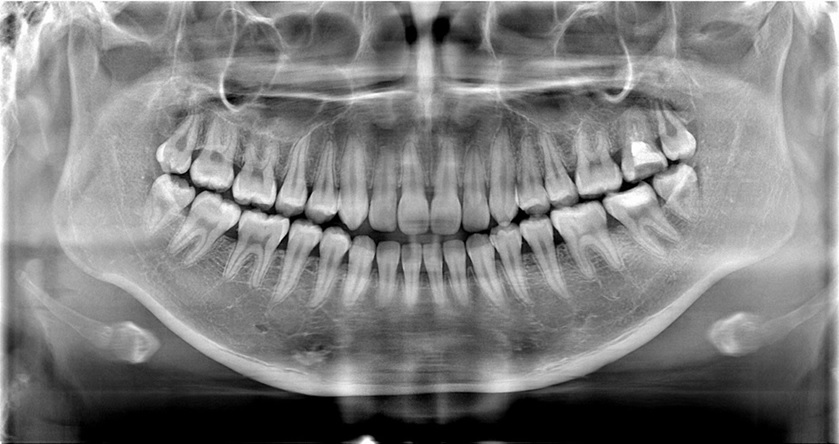

弊社レントゲン装置の特長は、☆ノイズが少ない高画質パノラマ画像、☆パノラマから14枚法の算定が認可された技術、☆CT値表示機能を搭載しています。

弊社商品“PanoACT 3D Upgrade”の特長は、歯科画像診断における4つの撮影(CT・パノラマ・デンタル・セファロ)が1台でできる待望の1台4役(オールインワン)装置です。宇宙工学で用いられている高感度CdTe半導体センサーおよび独自の画像処理技術を搭載し、パノラマ装置でありながらデンタルの診療報酬算定が初めて認可された装置です。 ☆PanoACT 3D Upgradeの独自の技術機能 1.優れた拡張機能のオールインワンCT装置(後からでもCT化やセファロ化が可能) 2.学術的に評価された鮮明なパノラマ画像、セファロ画像(宇宙工学のセンサー使用) 3.パノラマからデンタル請求可能(10枚・14枚法の請求も可能) 4.高解像度CT 5.金属アーチファクト低減機能 6.CT値(HU値 )表示機能 ご来場を心よりお待ち申し上げております。